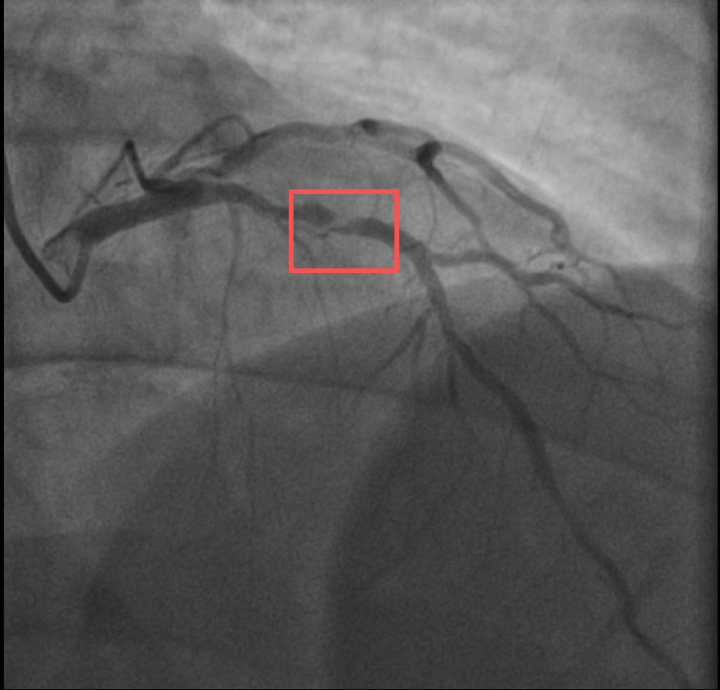

孙先生(化名)身高173cm,体重约90KG,是一位羽毛球教练。一年前,他因胸闷就诊时被查出心脏右冠中段、远端钙化斑块,以及心脏三支主要血管之一前降支中段60%狭窄。当时考虑到没有三高的危险因素(可能为早发冠心病家族史),孙先生也坚信自己可以通过运动恢复健康,因此拒绝了介入治疗,只接受药物治疗。

介入治疗前影像图

浙江医院心血管内科的医生分析,剧烈运动导致这位患者心脏的不稳定斑块破裂,进而造成前降支近段次全闭塞。所幸送医及时,孙先生的身体险情被化解。